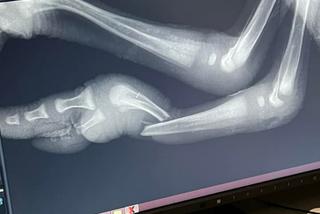

Osoba, która go przywiozła, ma całe stado strusi, a małego Tadzia miał kupić w takim stanie. Weterynarze przyjęli ptaka pod opiekę i jeszcze tego samego dnia wykonali operację ratującą życie. Struś dzielnie zniósł poważny zabieg. Teraz dostał gips i dochodzi do siebie w Ośrodku. -Przed nami długie leczenie i rehabilitacja. Tadzio bardzo potrzebuje tej nogi i zrobimy wszytko, aby mógł funkcjonować- mówił weterynarz Radosław Fedaczyński.

Struś ze złamaną nogą